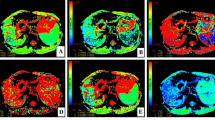

Figure 2 shows the DWI and ADCst, Dt, Dp, f, DDC, and α maps for a patient with fibrosis stage 2 and inflammatory activity grade 2. All parameters except Dp and α were significantly different among the control group and groups F1, F2, F3, and F4 (all P < 0.001) and showed a tendency to decrease gradually as the HF stage progressed (Fig. 3). Additionally, all parameters except Dp and α were significantly different among the control group and groups A1, A2, and A3 (all P < 0.001) and showed a tendency to decrease gradually as the inflammatory activity grade progressed (Fig. 4).

A 26-year-old female patient with CHB with fibrosis stage 2 and inflammatory activity grade 2. Diffusion-weighted image with b = 50 s/mm2 (a). The ADCst map showed that the ADCst value was 0.92 × 10−3 mm2/s (b). The Dt map showed that the Dt value was 0.67 × 10−3 mm2/s (c). The Dp map showed that the Dp value was 24 × 10−3 mm2/s (d). The f map showed that the f value was 25.9% (e). DDC map showed that the DDC value was 1.02 × 10−3 mm2/s (f). The α map showed that the α value was 0.70 (g)